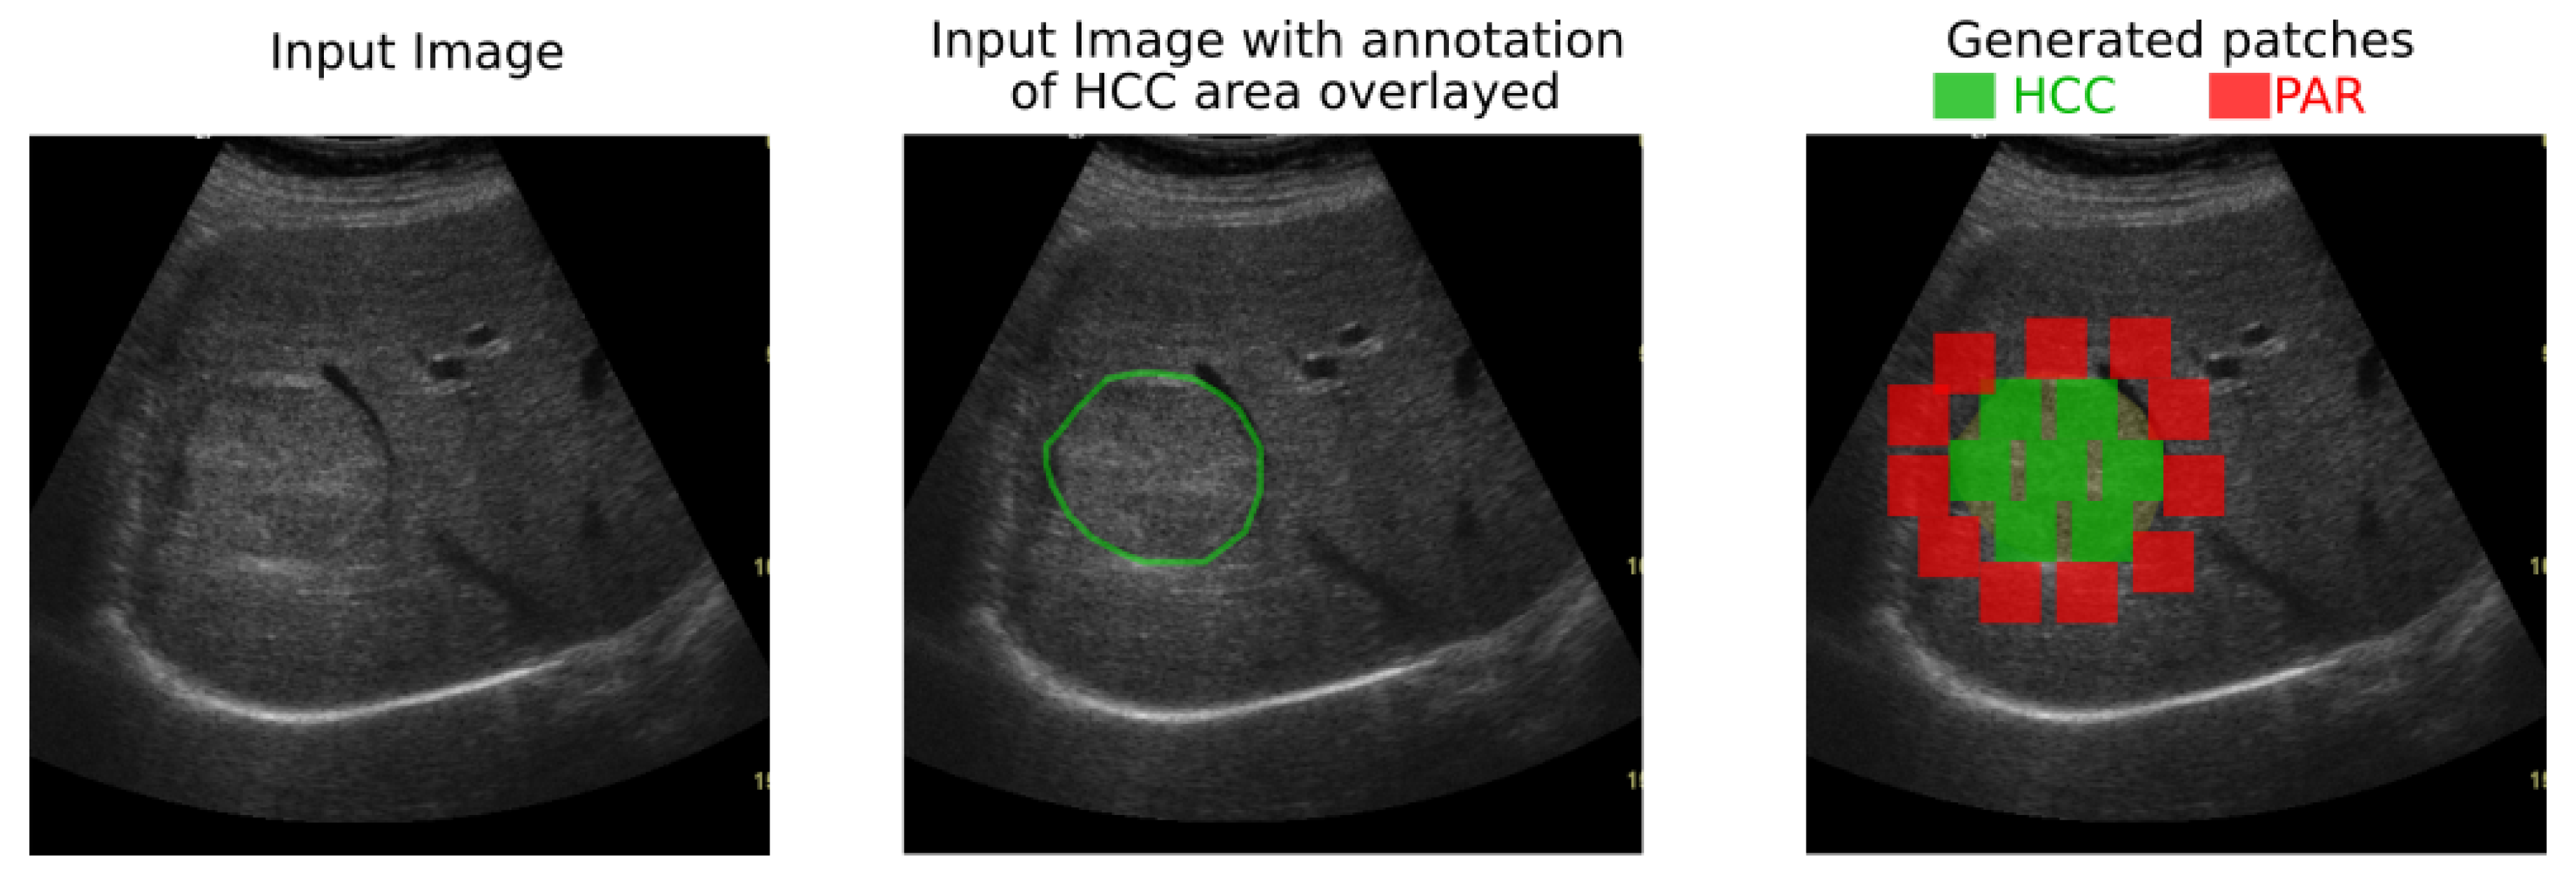

In both datasets, the HCC was marked as a polygonal area in the image, as shown in Figure 1—right, and Figure 2—middle. For each ultrasound image, considering the marked HCC area, rectangular image patches(regions) have been selected, by means of a controlled sliding window procedure. Part of these patches are located inside the annotated area and they correspond to the HCC class. The samples of the generated patches are depicted in green in Figure 2. Other patches are in the immediate vicinity of the polygonal annotation, but outside the marked HCC area. They correspond to the PAR samples and are shown in red in Figure 2. Cases of healthy patients were not considered because, usually, HCC evolves on cirrhotic liver tissue, for patients already affected by cirrhosis. The medical specialists suggested a focus on these two cases—to make the differentiation between HCC and the cirrhotic parenchyma on which it evolved, while healthy tissues have not been included in this study.

Due to the nature of the tumors, due to the small area they occupy in the ultrasound images and in order to ensure at least one valid HCC and one valid PAR region per annotation, a size of 56 × 56 pixels was selected for the regions of interest. The ultrasound image is traversed with a sliding window of size 56 × 56 pixels. If the window is inside the marked area, and its intersection with any other generated patch is smaller than 0.1% of their union, then the window is added to the set of HCC generated patches. If the window is outside the HCC marked area but one of its corners is on the boundary of the marked region and its intersection with any other patch is smaller than 0.1% of its area, we add it to the set of the PAR patches. To ensure variety and diversity in the selected image samples a minimal intersection factor of 0.1% was considered when generating the regions of interest.

Depending on the size of the HCC annotated area and on the number of annotated images for a patient, at least 3 HCC patches and 5 PAR patches have been generated for each patient. The selection was validated by medical specialists.

Figure 2. Generation of HCC and PAR patches of 56 × 56 pixels by scanning the marked area and its close exterior.

Sensors 20 03085 g002